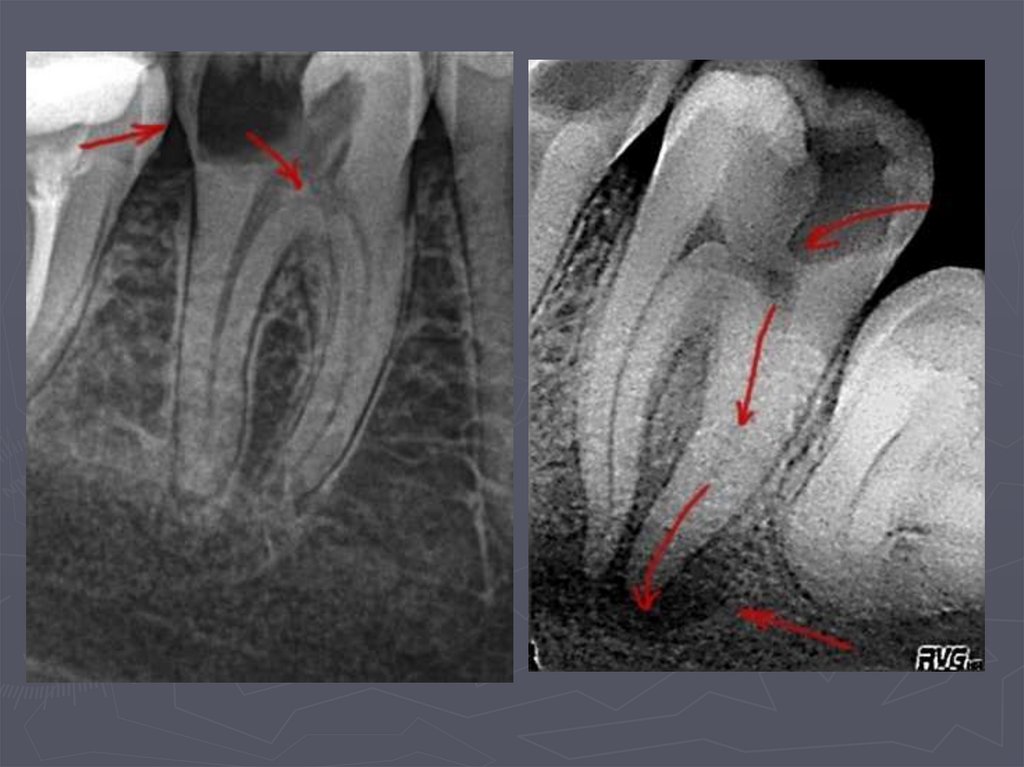

РЕНТГЕНОЛОГИЧЕСКИЙ МЕТОД –

применяется:

в случаях крайнего затруднения

диагностики,

► при локализации полостей на

апроксимальных поверхностях,

► при тесном положении зубов.

93. Кариес на рентгеновских снимках

94. Рентгенологическая классификация кариеса

95. МЕТОДЫ ДИАГНОСТИКИ КАРИЕСА У ДЕТЕЙ